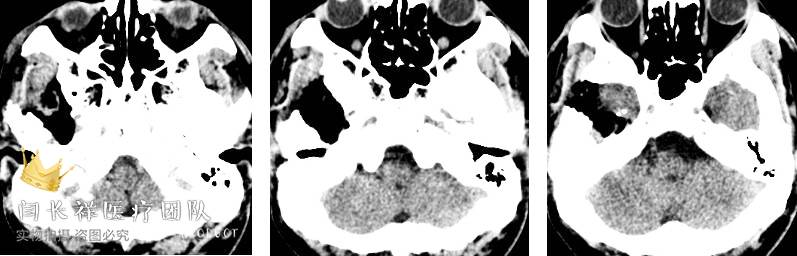

术前冠位CT示右侧中颅窝、颞下窝、翼腭窝占位,病灶呈稍高密度。

术前矢状位CT。

术前冠位CT骨窗像示右侧中颅窝底骨质被肿瘤侵蚀破坏。